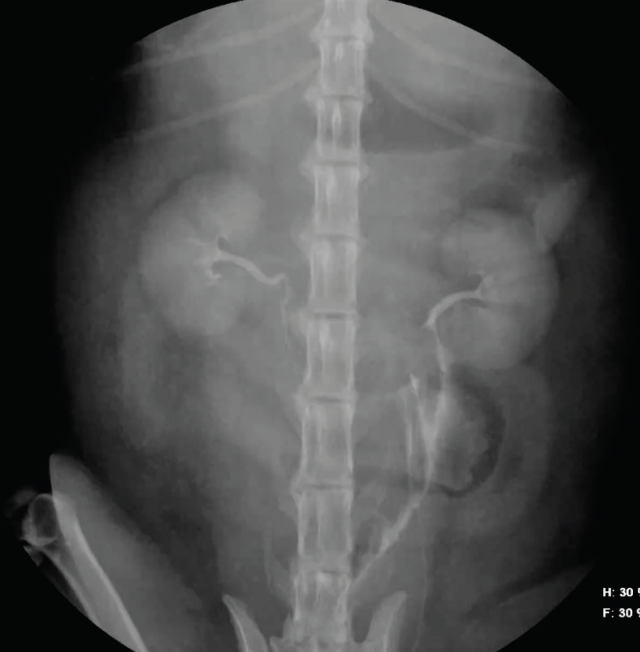

Urinary tract rupture can also occur with pelvic injury. A palpable bladder and the ability to urinate does not exclude urinary tract trauma (Aumann 1998). Baseline blood work indicating azotaemia and hyperkalaemia and a point-of-care ultrasound indicating abnormal abdominal fluid can help confirm a uroabdomen. Abdominocentesis and fluid analysis can provide further confirmation: in one case series the mean ratio of serum to peritoneal effusion for creatinine and potassium was 2:1 and 1.9:1 respectively (Aumann 1998). The perineal area should also be assessed for subcutaneous leakage from caudal urethral ruptures, but skin necrosis may take 24-48 hours to develop. A contrast study should be performed if there is confirmation of rupture or any uncertainty of patency (Figures 11 and 12). In the author’s institute, an intravenous urethrogram is generally performed prior to a retrograde urethrogram to confirm the ureters are patent.